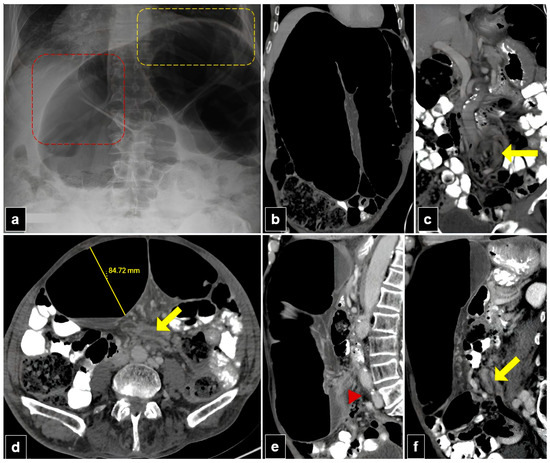

Figure 4. A 77-year-old male patient with organo-axial sigmoid volvulus presented with abdominal pain and distension for two days. (a) The plain abdomen radiograph reveals significant distension of the sigmoid loop, characterized by an inverted “U” shape, liver overlap sign (red dashed quadrilateral), and the sigmoid apex located beneath the left hemidiaphragm sign (yellow dashed quadrilateral). (b,c) Abdominal computed tomography (CT) images in the coronal plane show the inverted U-appearance of the distended sigmoid loop, and only one transition zone is present. Note the split wall sign caused by mesenteric fat tissue at the level of the transitional zone (yellow arrow). (d) The axial plan abdominal CT image shows the degree of distension in the sigmoid colon and the split wall sign located in the transition zone (yellow arrow). (e,f) The sagittal plane CT images of the abdomen show a single transition zone (red arrowhead) and a split wall sign (yellow arrow).